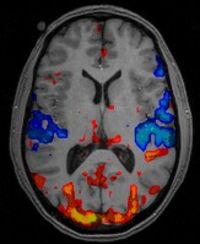

Individuals with schizophrenia shows a wide range of cognitive deficits, and lack in the ability to control the variety of inputs (whether internal or external) to create a unitary “self”. This problem has been often associated with a supramodal attentional deficit, but its causes are yet unknown. In the past twenty years, the quest to identify brain regions or networks showing abnormal functioning in schizophrenia has been unproductive; but one question is left unanswered: is it possible that it is the white matter tracts supporting attention (i.e., the superior longitudinal fasciculi I, II, and III) to be compromised in this psychiatric disorder? The present project will attempt to dissect the fronto-parietal branches with DTI by analyzing over 400 images from the Open Access SchizConnect.Org repository (data already available to the PI). Funds will be used to support the work of a junior or senior-year undergraduate student (possibly from URMs) to conduct the data analysis during the summer of AY2020. Results will be made available with the scientific community and published in open access peer-review journals (e.g., Schizophrenia Research). Co-mentoring of the undergraduate student will be done by Dr. Henrietta Howells (https://scholar.google.it/citations?user=nudmODkAAAAJ&hl=en&oi=ao), opening the student to an international collaboration.